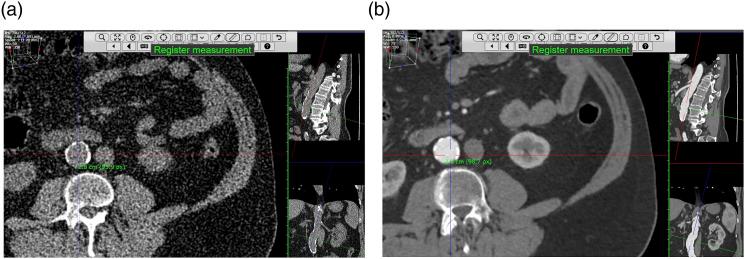

To determine whether ultra-low-dose non-contrast CT (ULDNC-CT) can be used instead of the gold standard CT angiography (CTA) for assessment of maximal abdominal aortic diameter.

This retrospective study included 50 patients who underwent CTA and a normal-dose non-contrast CT for suspected renal artery stenosis. ULDNC-CT datasets were generated from the normal-dose non-contrast CT datasets using a simulation technique. Using the centerline technique, radiology consultants ( = 4) and residents ( = 3) determined maximal abdominal aortic diameter. The limits of agreement with the mean (LOAM) was used to access observer agreement. LOAM represents how much a measurement by a single observer may plausibly deviate from the mean of all observers on the specific subject.

Observers completed 1400 measurements encompassing repeated CTA and ULDNC-CT measurements. The mean diameter was 24.0 and 25.0 mm for CTA and ULDNC-CT, respectively, yielding a significant but minor mean difference of 1.0 mm. The 95% LOAM reproducibility was similar for CTA and ULDNC-CT (2.3 vs 2.3 mm). In addition, the 95% LOAM and mean diameters were similar for CTA and ULDNC-CT when observers were grouped as consultants and residents.

Ultra-low-dose non-contrast CT exhibited similar accuracy and reproducibility of measurements compared with CTA for assessing maximal abdominal aortic diameter supporting that ULDNC-CT can be used interchangeably with CTA in the lower range of aortic sizes.